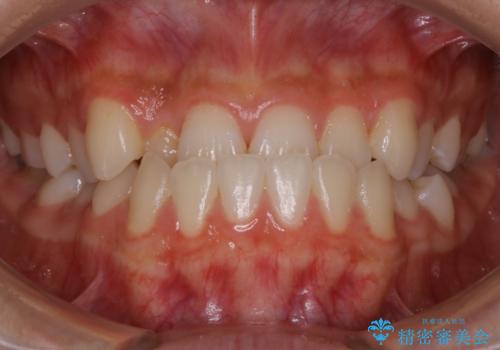

【非抜歯】受け口の改善 10代で始める本格的噛み合わせ治療

- 受け口の改善と前歯のガタつきの治療を主訴にご来院されました。

こちらの患者様の場合、上の前歯のガタつきが原因で口を閉じる際に上下の前歯の先端同士が先に当たってしまい、そこからさらに深く噛み込もうとすると下顎が前にずれていってしまうという、機能性の反対咬合であることが検査の結果わかりました。

そのため、まずは上顎の前歯のガタつきを改善していき、前歯が先に当たってしまうという症状を改善し噛み込む位置を後方の本来の位置に誘導する方法をとりました。